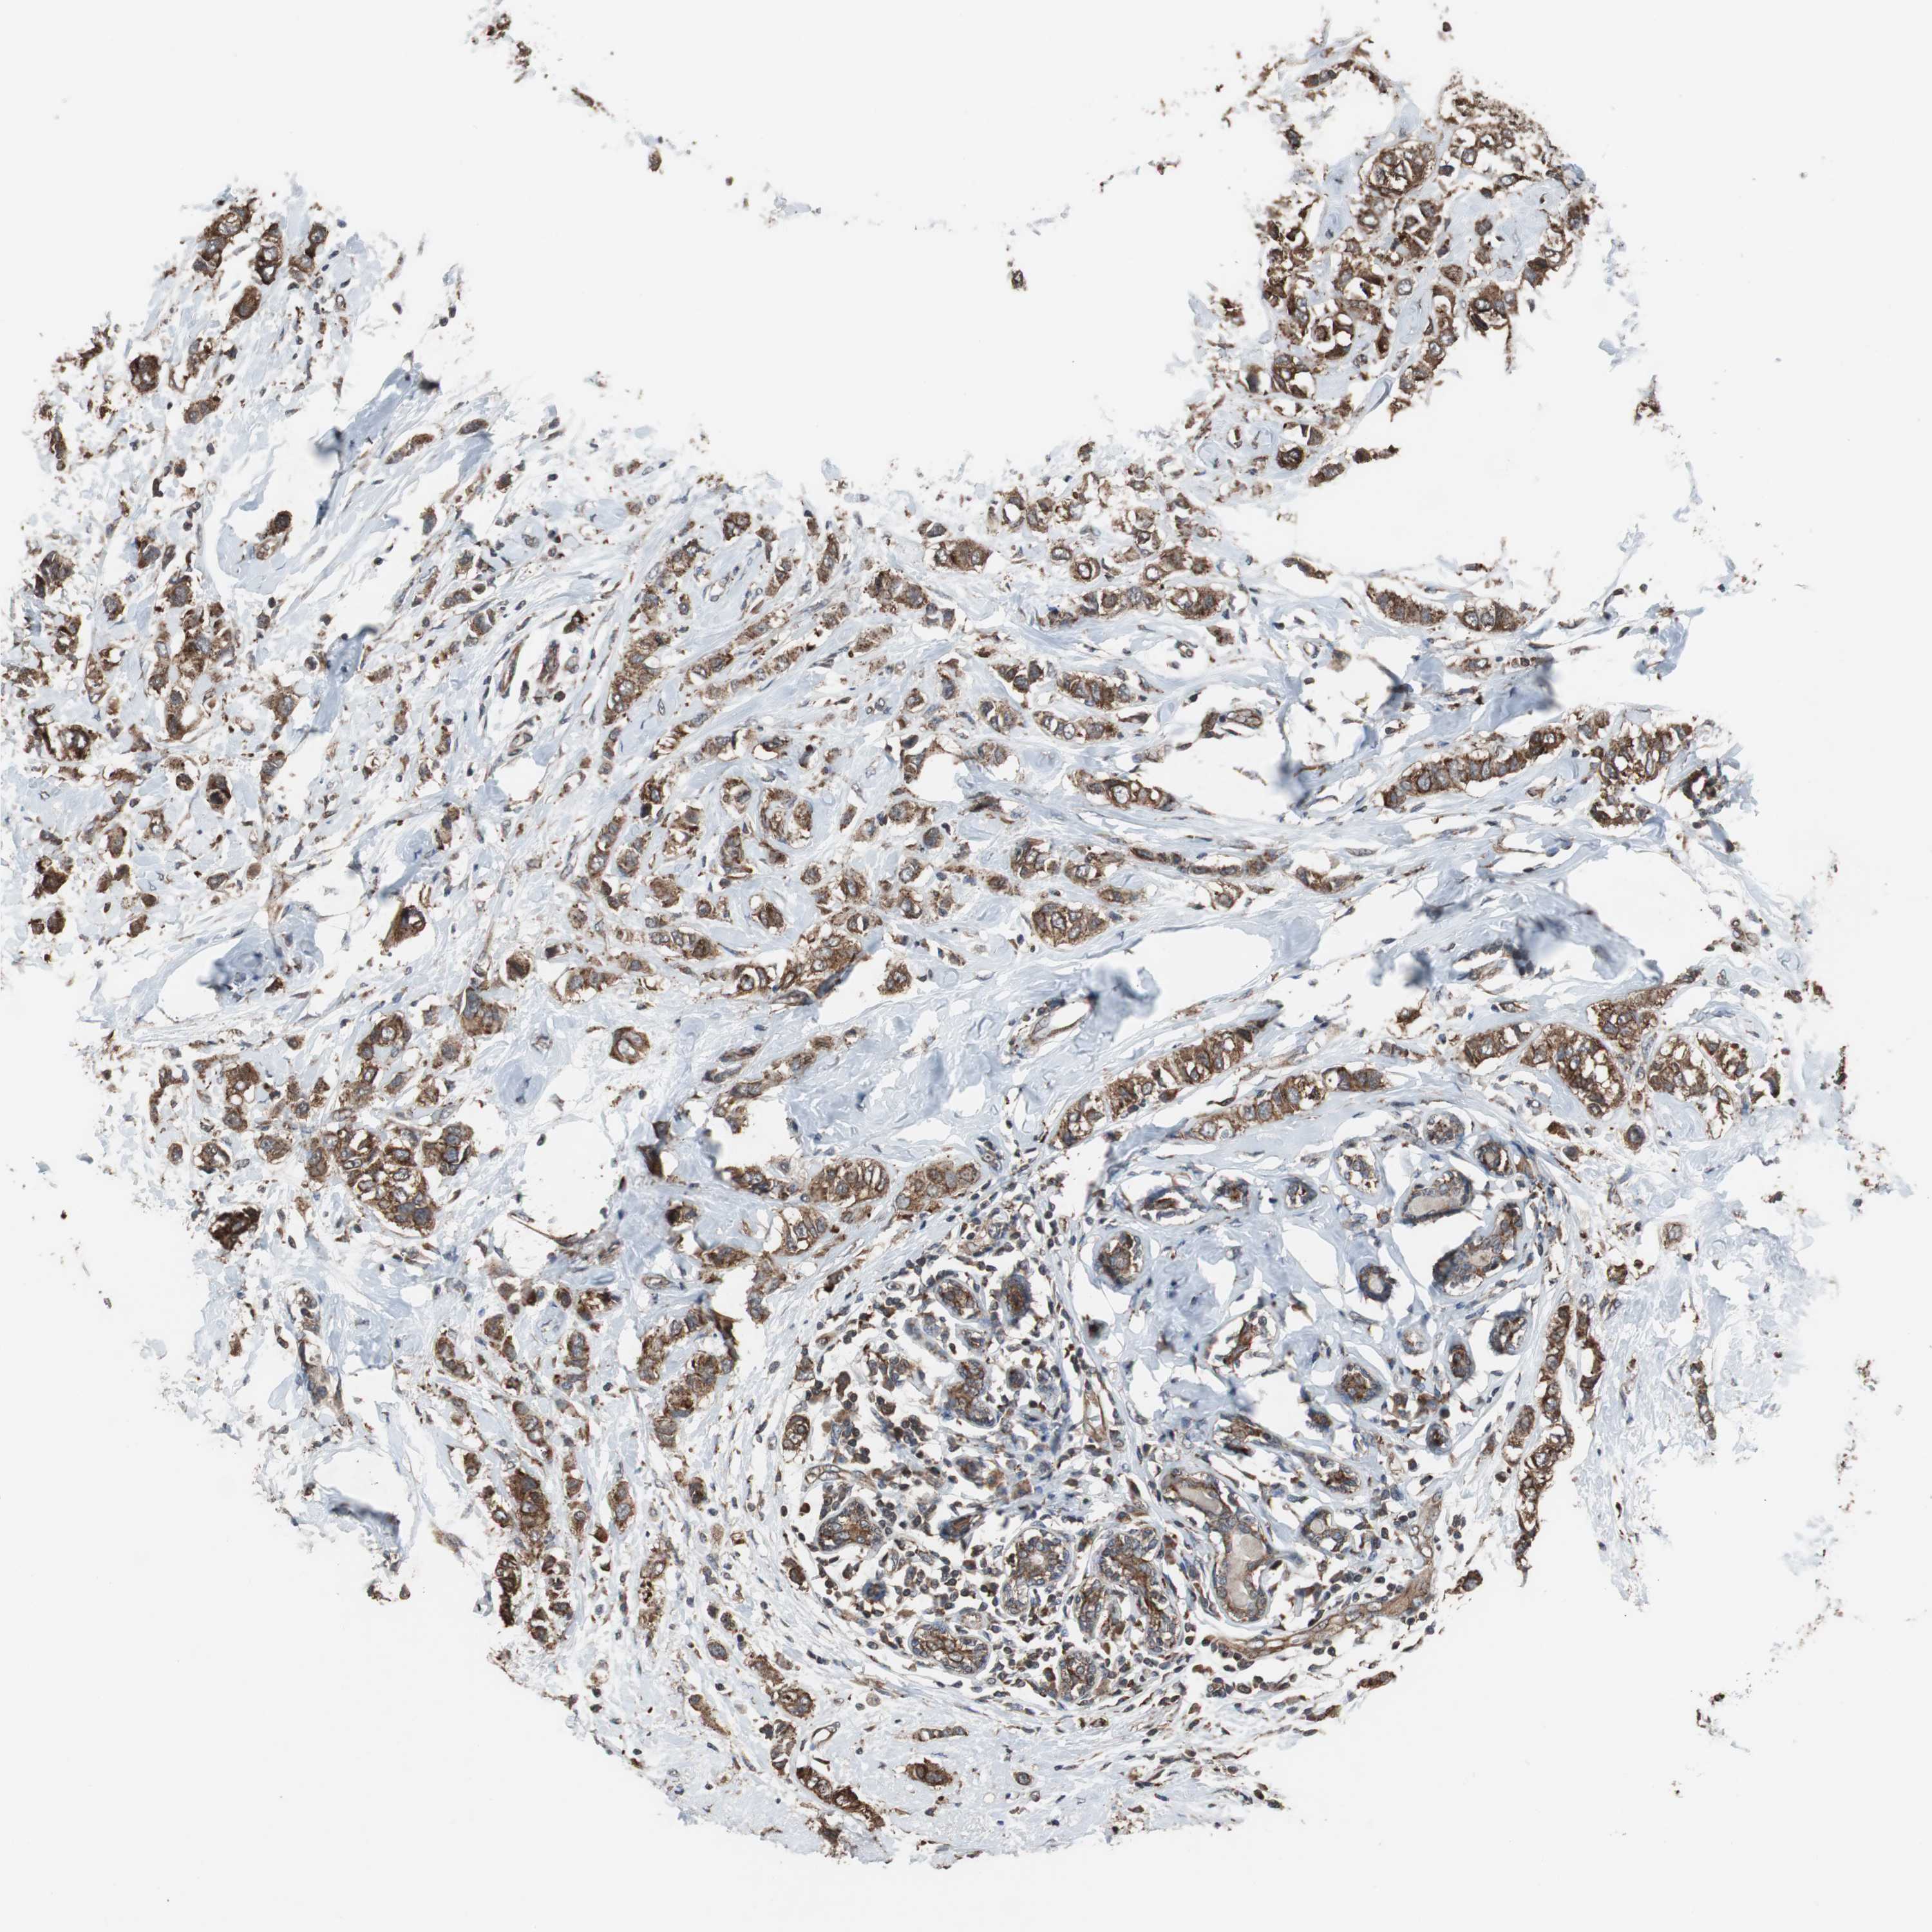

CANCER BREAST CANCER Show tissue menu

BRCA TCGA BRCA VALIDATION PROTEIN EXPRESSION